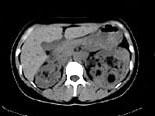

问题 女,36岁,左侧腰痛2 年余,CT检查如图所示,下列说法错误的是 ( )

选项 A、考虑为肾癌 B、考虑为双肾错构瘤 C、左肾病灶中可见脂肪密度灶,该区增强时也无强化 D、右肾中极可见一小的类圆形混杂密度病灶 E、左肾下极可见一混杂密度病灶,其边界尚清

答案 A